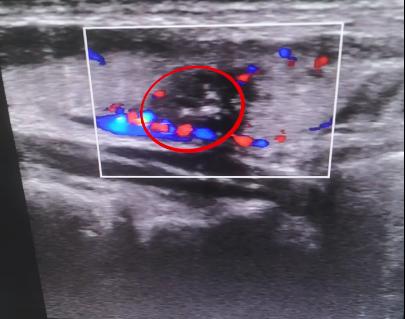

到院后给患者安排了更精密的 四维弹性成像 检查,病灶区域显示得比彩超清晰许多。

检查结果显示,常先生的 甲状腺结节紧邻甲状腺被膜,一旦突破会有转移的风险 ,建议常先生抓紧治疗。

局部麻醉后,在四维弹性成像的精准定位下,25分钟为患者完成了手术,手术很成功,微创介入技术迅速灭活病灶区域结节活性, 没有损伤周围组织及腺体。

住院观察3天后,患者康复出院, 7月26日来复查时,四维弹性成像检查显示病灶区域已经完全消融吸收 ,只要注意遵从医嘱,定期复查,就不会对生活造成影响。